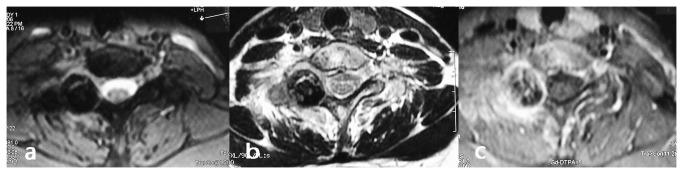

From June 2006 to July 2011, 18 patients with spinal osteoblastoma treated surgically were analyzed retrospectively. There were 11 males and 7 females with an average age of 27.5 years(range, 16-38 years). The tumors were located at C5 in 7, C6 in 6, C7 in 3, C6-T1 1 in 1 and T11 in 1. Based on WBB classification, 16 were 1-3 or 10-12 and 2 were 4-9 and 1-3. 18 operations had been performed with en bloc resection. A posterior approach was used for 16 patients, and a combined posterior and anterior approach was used for 2 patients. Reconstruction using instrumentation and fusion was performed using spinal instrumentation in 13 patients. We used visual analogue scales (VAS) to evaluate the change of pain before and after the operation, and the McCormick System to assess functional status of the spine. Imaging test was used to review the stability and recurrence rate of spine cord, and the confluence of graft bones.

All cases were followed up for 24-80 months (average, 38.4 months). The average surgical time was 120.8 minutes (range, 80-220 minutes), with the average intraoperative blood loss of 520 ml (range, 300-1200 ml). During the follow-up period, the VAS grade reduced from 6.46±1.32 to 2.26±1.05 (P <0.05). 15 patients had neurological function improved and 3 remained no change which was evaluated by McCormick scale for spinal function status at final follow-up.

Spinal osteoblastoma has its own specific radiographic features. There is some recurrence in simple curettage of tumor lesion. The thoroughly en bloc resection of tumor or spondylectomy, bone fusion and strong in Ter fixation are the key points for successful surgical treatment.